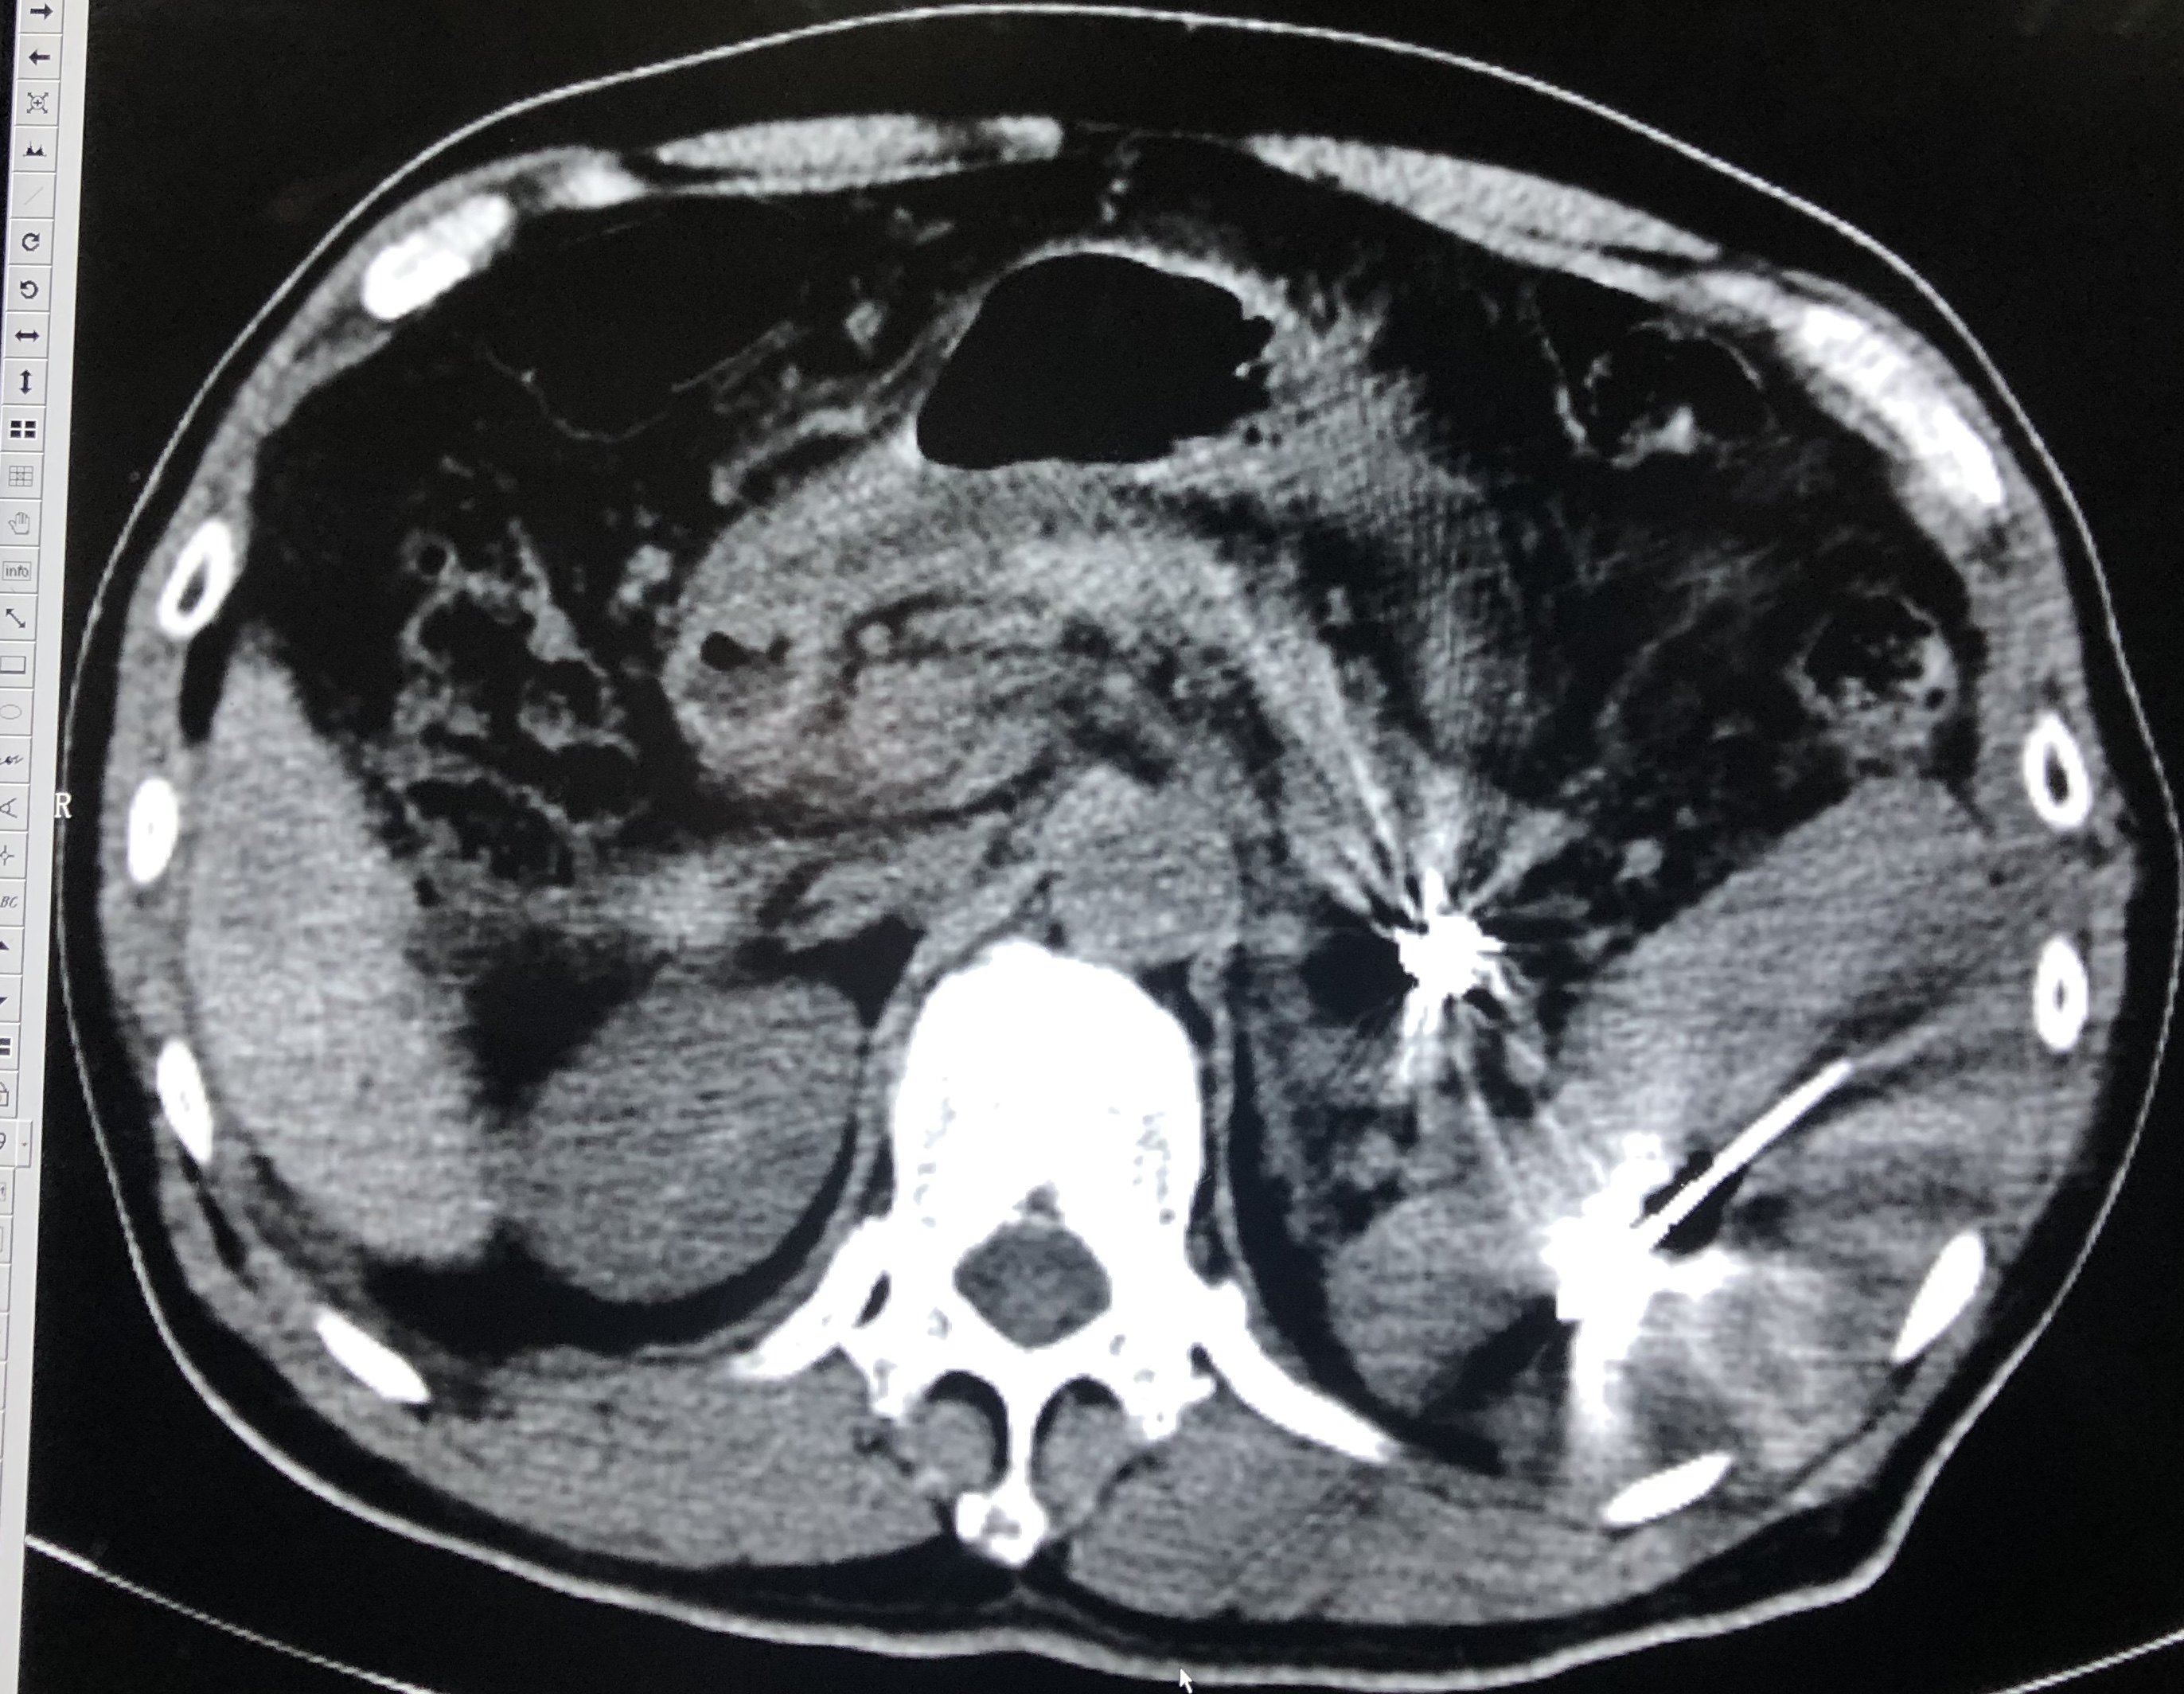

右肝肿瘤门脉期低密度,为肝癌典型表现。